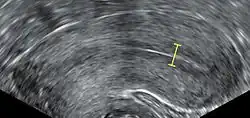

Egg retrieval

The eggs are retrieved from the patient using a transvaginal technique called transvaginal ultrasound aspiration involving an ultrasound-guided needle being injected through follicles upon collection. Through this needle, the oocyte and follicular fluid are aspirated and the follicular fluid is then passed to an embryologist to identify ova. It is common to remove between ten and thirty eggs. The retrieval process, which lasts approximately 20 to 40 minutes, is performed under conscious sedation or general anesthesia to ensure patient comfort. Following optimal follicular development, the eggs are meticulously retrieved using transvaginal ultrasound guidance with the aid of a specialised ultrasound probe and a fine needle aspiration technique. The follicular fluid, containing the retrieved eggs, is expeditiously transferred to the embryology laboratory for subsequent processing.[55]